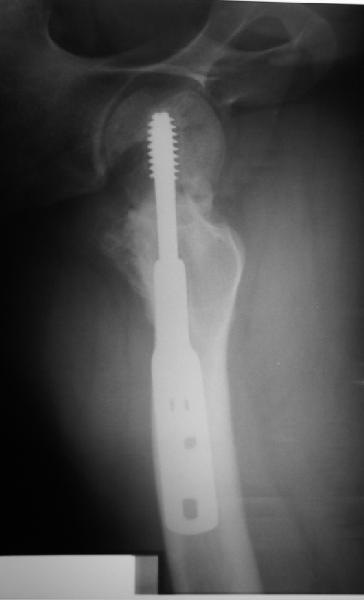

Я бы ограничился вальгизацией без вмешательства в зону перелома шейки. Биология здесь, надо полагать, хорошая, необходимо только улучшить механическую составляющую.

В итоге что-то такое и сделали. Убрали DHS, остеотомия, синтезировали Affixus с небольшой вальгизацией. Снимки в приложении.

Ну, чтож, теперь будем посмотреть).

Интересен результат через 6-12-24-и т.д. месяцев

Похоже удалось провести шеечный винт мимо старого канала, и вальгус, вроде, удался. Только хороший-ли контакт фрагментов в зоне остеотомии? Действительно - жизнь покажет.